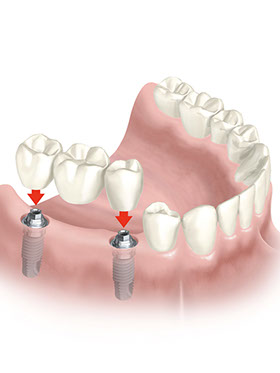

L’assemblaggio tra Impianto e Protesi

Tolta definitivamente la Vite di Guarigione si avvitano i Pilastri, ciascuno per ogni Impianto.

Ogni Pilastro farà da sostegno alla Protesi.